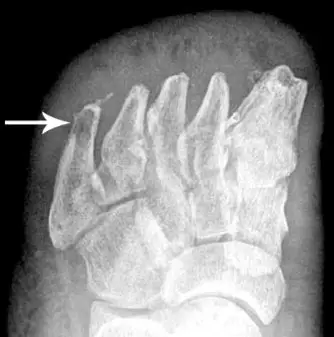

第五跖骨的透亮影,提示骨髓炎